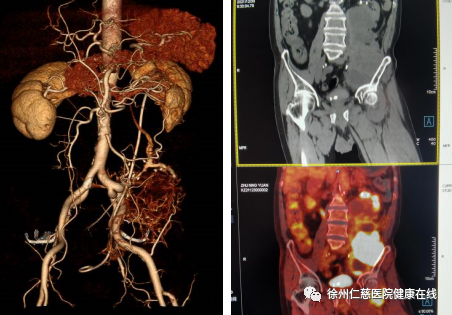

后来来到徐州仁慈医院。普外科韩锡琳主任接诊时发现袁大爷的肿瘤体积为 29*10*7 cm,并且已经包裹输尿管及部分肾脏,侵犯左侧股神经,压迫大血管。通过与袁大爷的沟通,了解其目前被病痛折磨的无法正常生活,放、化疗对其无效,手术是唯一希望,韩主任立即安排袁大爷住院接受治疗。

1 月 3 日,由介入科陈育峰主任在局麻下为患者行腹腔动脉造影+肿瘤动脉栓塞术,栓塞肿瘤主要供血血管 5 根,尽可能切断肿瘤血供,为第二天的手术创造条件。

9 时 9 分开始手术。开腹后,普外科主任韩锡琳和泌尿外科主任王甫剑沿降结肠旁沟切开后腹膜,沿腹膜后向右侧分离,发现肿瘤边界不清,肾门血管及输尿管无法显露,当机立断决定行腹膜后肿瘤连同左肾一并切除。